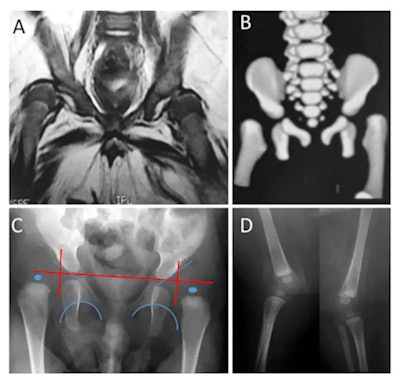

The seven children underwent neurological and orthopedic examinations along with several other investigations: radiography, brain CT, or brain MRI without contrast, high-definition ultrasound of the joints (with specific attention to cartilage, synovia, pericapsular structures, and muscular tissue around joints), nerve conduction studies, and needle electromyography. If calcifications were present on brain imaging (CT or MRI), the researchers considered the possibility of congenital infections. Four children underwent MRI of the spine. MRI was not possible in two children as they were receiving mechanical ventilation on an intensive unit care.

All children showed signs of brain calcification. The theory is the Zika virus destroys brain cells, and forms lesions on which calcium is deposited. There was no evidence of joint abnormalities. This led van der Linden et al to note the arthrogryposis did not result from abnormalities of the joints themselves, but was likely to be of neurogenic origin, leading to fixed postures in the womb and consequently deformities.